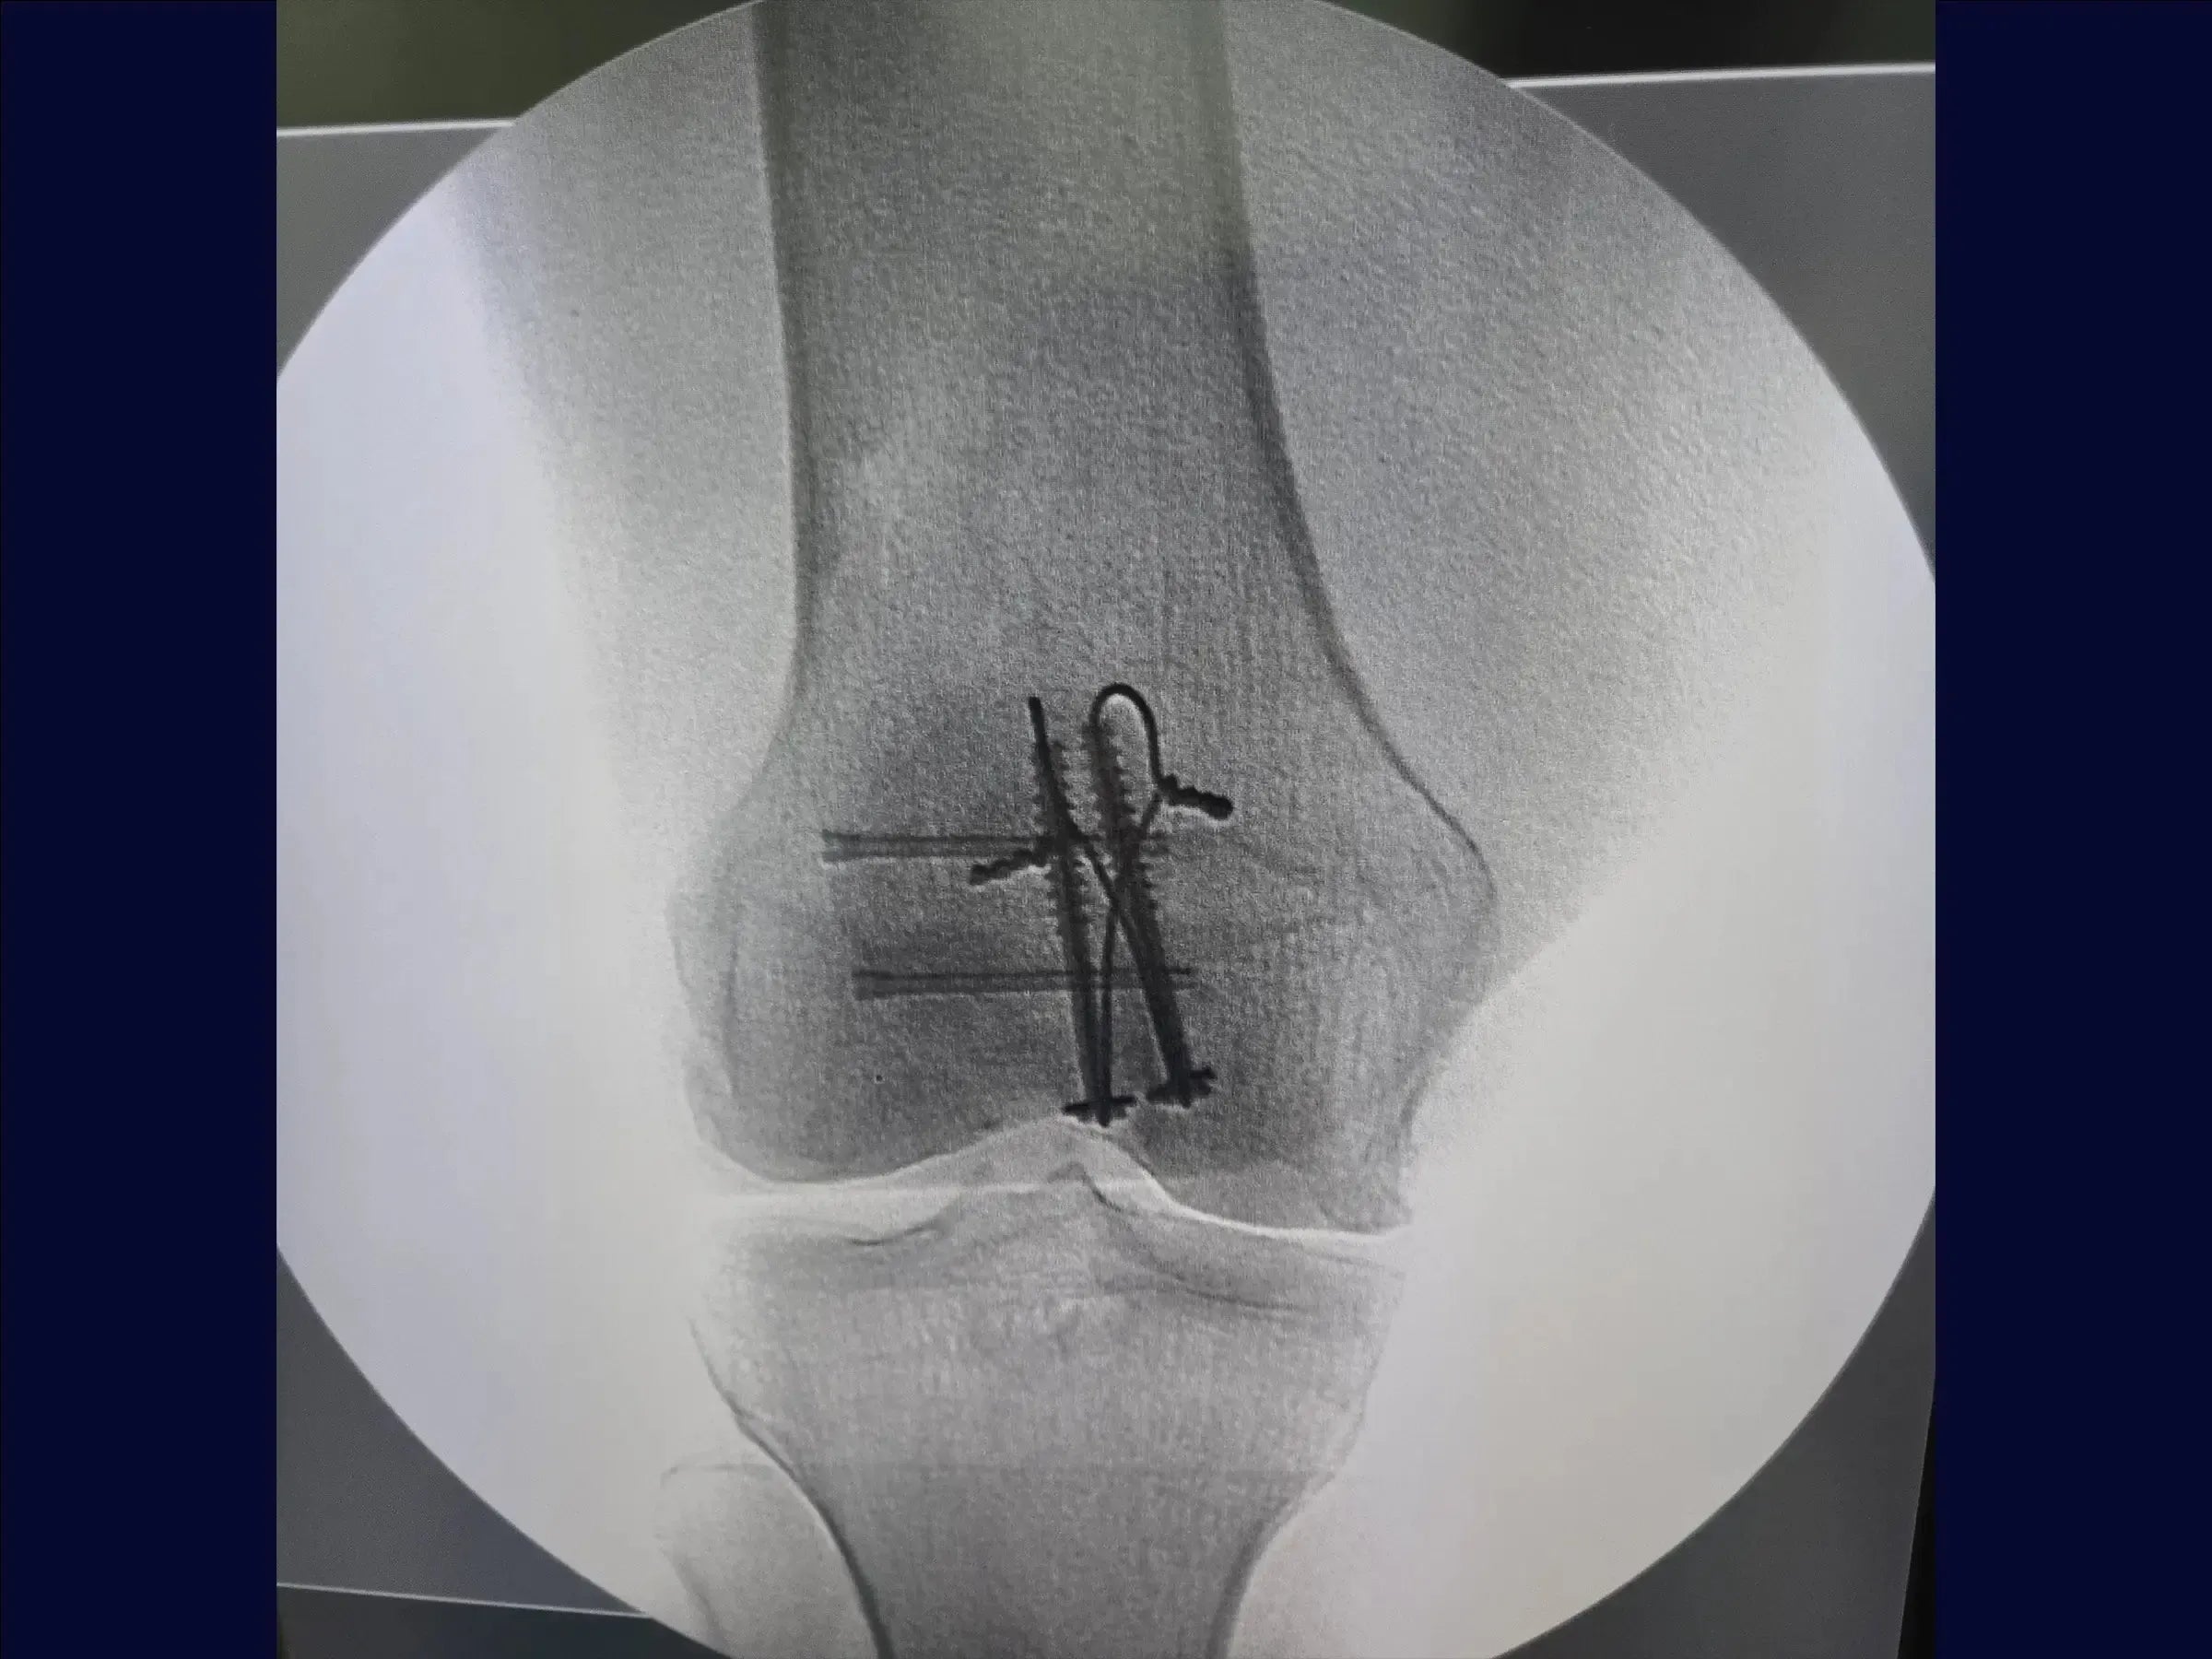

- Uso de parafusos canulados e cerclagem.

- Fixação de Fragmentos Laterais: Utilização de parafusos de dupla compressão para fixação de fragmentos na aleta lateral, com sepultamento completo da cabeça para prevenir proeminência do implante.

- Identificação do Fragmento Chave: Foco na importância do polo inferior inserido ao tendão patelar como ponto crucial para a redução e concentração de parafusos com arruela para estabilização.